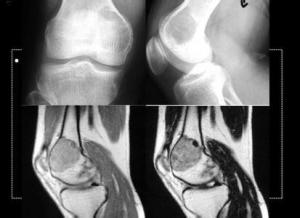

软骨黏液样纤维瘤(chondromyxoid fibroma)是一种较少见的良性骨肿瘤,该肿瘤系起源于成软骨性结缔组织,Jaffe将其命名为“软骨黏液样纤维瘤”,主要是依据其组织学特征,组织学表现既有软骨样组织,同时在黏液样基质内有些巨核的或异形细胞,以往容易被误诊为软骨肉瘤。[1]